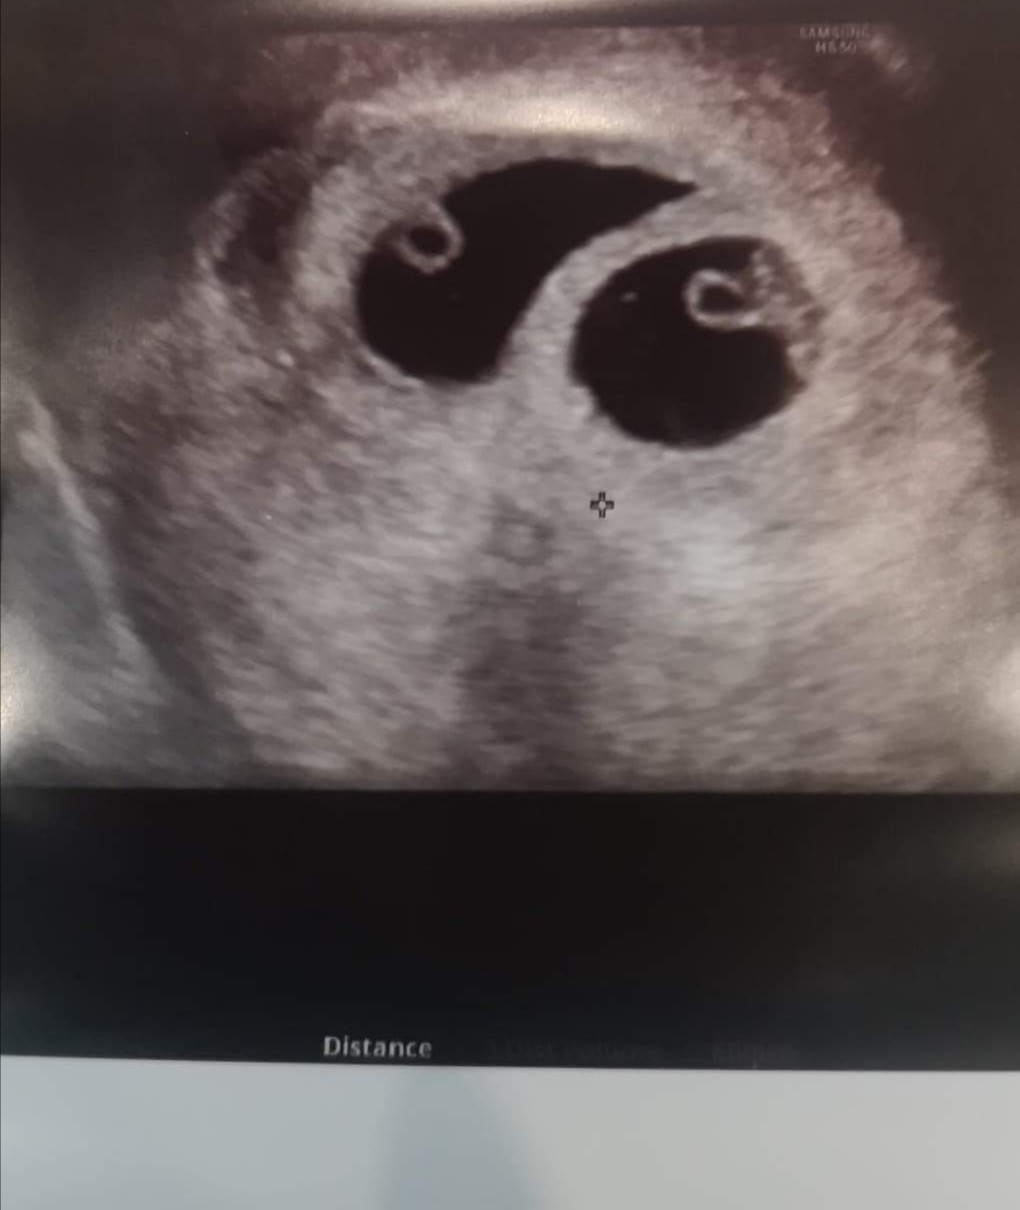

Cudny widok. Współczuję stresu i naprawdę składaj skargę. Jak można przeoczyć dwa zarodki?